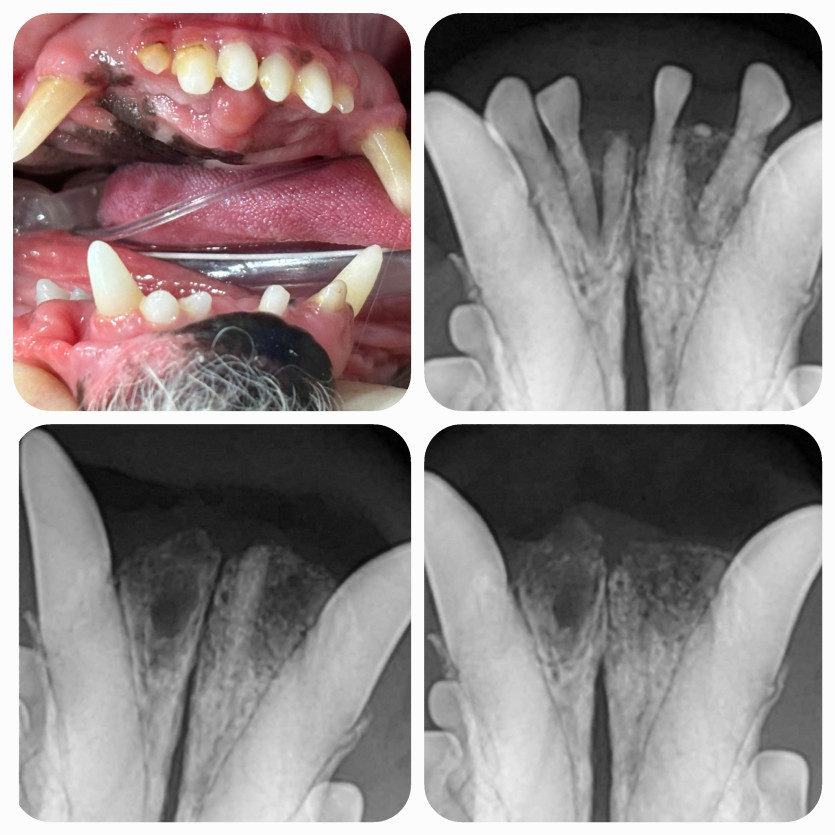

사막이의 잔존치근 치료후기

노령견이라 마취하고 안깰까봐 많이 걱정되었었는데

꼼꼼한 검사와 세밀한 체크 & 진료 덕분에 안심하고 진료 받았습니다.

수술 후에도 꼼꼼히 챙겨봐 주셔서 더 좋았어요.

안심하고 맡길 수 있는 병원인 것 같아요!!